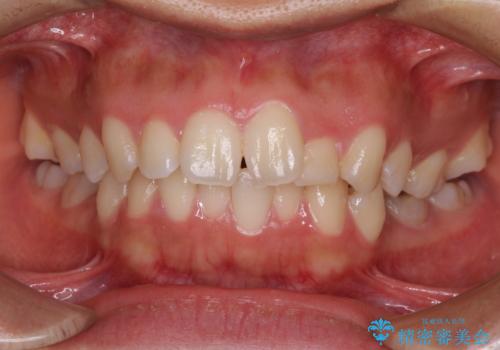

【モニター】捻れた前歯をスッキリと インビザライン矯正治療

担当医 藤巻太一朗